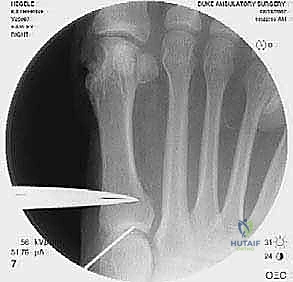

2. التصوير الشعاعي المتقدم

- الأشعة السينية مع تحمل الوزن (Weight-bearing X-rays): صور من الأمام، الجانب، والزوايا المائلة لتقييم زوايا العظام تحت تأثير وزن الجسم.

- تصوير السمسمانيات (Sesamoid view): لمعرفة ما إذا كانت العظام السمسمانية قد خُلعت من مكانها.